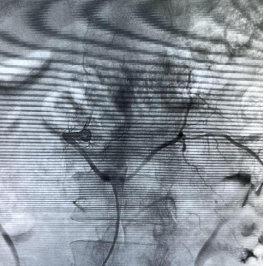

术前可见粗大的引流静脉

2023年4月2日,仇汉诚教授抵达广元后立即赶往市第一人民医院准备手术。当天下午,仇汉诚教授带领神经外科团队在复合手术室内,于全麻下为患者行脊髓血管造影+硬脊膜动静脉瘘介入栓塞术,术中可见L1肋间动脉分支供血,供血动脉迂曲纤细,引流静脉粗大。到达瘘口的“路径”建立困难,经历2小时的苦战,“神外天团”终于成功栓塞瘘口。

术后瘘口及引流静脉消失

术后,患者腰部及左下肢疼痛立即消失,臀部麻木感消失,下肢感觉麻木明显好转,右下肢肌力好转,达到II级。1周后,患者转回当地医院继续康复治疗。